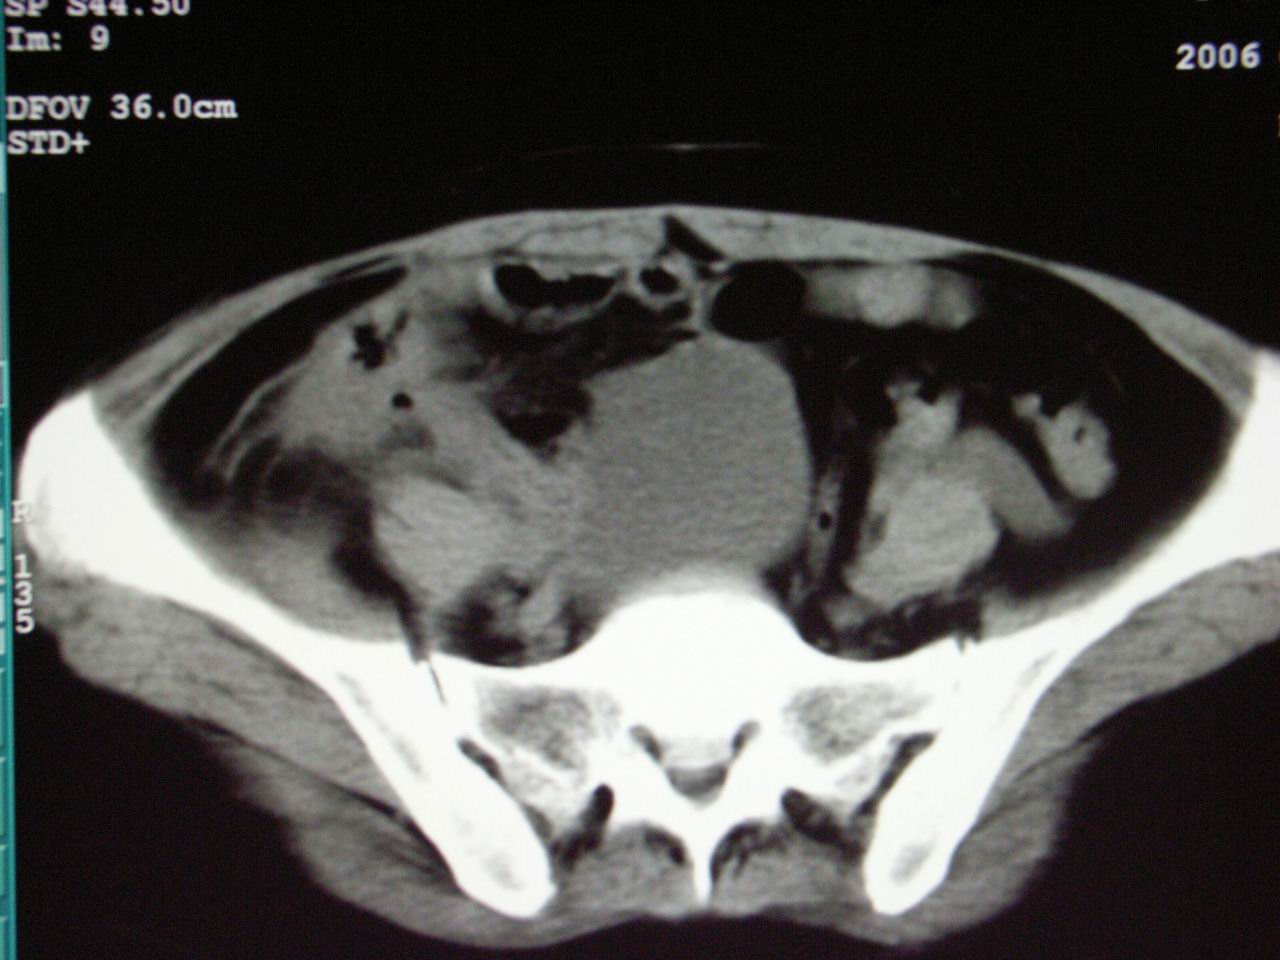

男;67岁,腹胀,腹痛,便血半年;钡餐透视发现右下腹部占位性病变

ct表现;病灶成环状软组织肿块,表现为不对称的肠壁增厚;肠腔变型.

升结肠肠壁不均匀增厚,肠腔变形,支持结肠癌.

支持结肠癌诊断,周围受累。